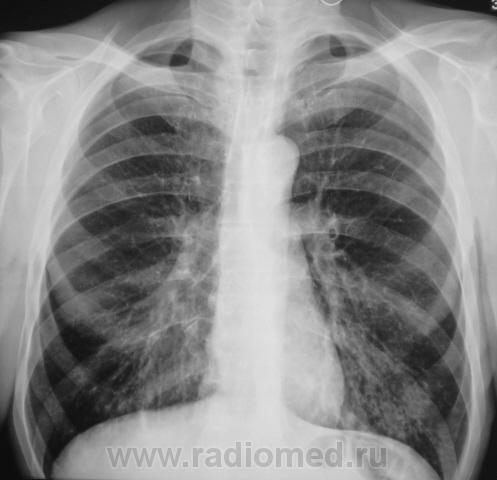

Пациент направлен на рентгенографию ОГК с диагнозом - "Левостороняя пневмония".

Анамнез стандартный. Ранее неоднократно страдал обострениями хронического бронхита. Сейчас вот не нашутку занемог - температура до 38, откашливает мокроту, кашель продуктивный.

Диагноз левосторонней нижнедолевой С10, С9 сементарной пневмонии наверное будет верным, а с учётом фона- с наличием бронхоэктазов.